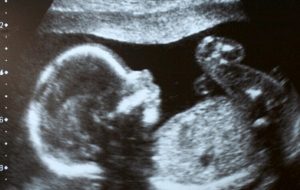

Plasentada İlk Kez Mikroplastik Parçacıklar Bulundu. Anne karnındaki bebekleri sarmalayan plasentada ilk kez mikroplastik parçacıklar bulundu; araştırmacılar bunun “çok kaygı